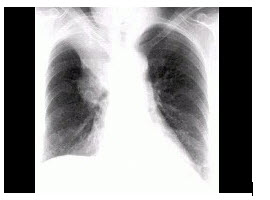

5、单项选择题

男,66岁,咳嗽、发热2周余,无痰中带血,X线检查如图,最可能的诊断是()

A.细支气管肺泡癌

B.血行播散型肺结核

C.左肺浸润型肺结核

D.左肺炎症

E.肺转移瘤